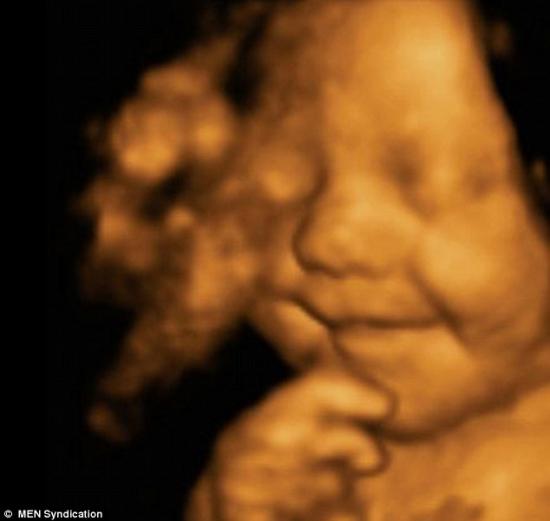

在孩子母亲怀孕31周时,她曾前往医院做了超声波成像,然而令她和她丈夫惊讶的是,自己肚子中的宝宝一直乐呵呵地微笑着。